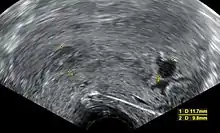

Ultrasound criteria

A review article in The New England Journal of Medicine based on a consensus meeting of the Society of Radiologists in Ultrasound in America (SRU) has suggested that miscarriage should be diagnosed only if any of the following criteria are met upon ultrasonography visualisation:[97]

| Crown-rump length of at least 7 mm and no heartbeat. | Crown–rump length of less than 7 mm and no heartbeat. | [97][98] |

| Mean gestational sac diameter of at least 25 mm and no embryo. | Mean gestational sac diameter of 16–24 mm and no embryo. | [97][98] |

| Absence of embryo with heartbeat at least 2 weeks after an ultrasound scan that showed a gestational sac without a yolk sac. | Absence of embryo with heartbeat 7–13 days after an ultrasound scan that showed a gestational sac without a yolk sac. | [97][98] |

| Absence of embryo with heartbeat at least 11 days after an ultrasound scan that showed a gestational sac with a yolk sac. | Absence of embryo with heartbeat 7–10 days after a scan that showed a gestational sac with a yolk sac. | [97][98] |

| Absence of embryo at least 6 weeks after last menstrual period. | [97][98] | |

| Amniotic sac seen adjacent to yolk sac, and with no visible embryo. | [97][98] | |

| Yolk sac of more than 7 mm. | [97][98] | |

| Small gestational sac compared to embryo size (less than 5 mm difference between mean sac diameter and crown-rump length). | [97][98] |